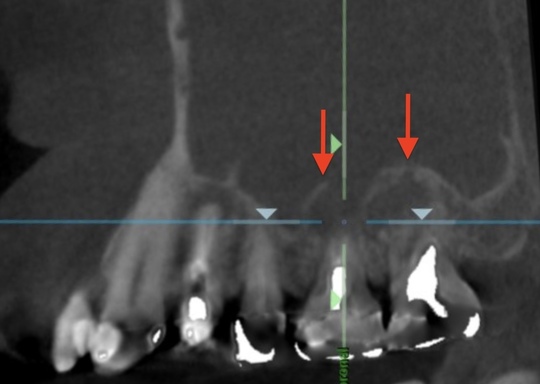

自費根管治療症例1 治療前

左上の奥歯の腫れと噛んだ時の痛みで来院。

根の先にうみが溜まっています

副鼻腔の骨の壁を突き破っています